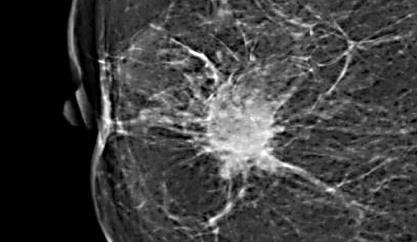

Mulher, 48 anos, apresenta lesão palpável em mama direita. A mamografia evidencia o seguinte achado (figura 4).

Figura 4: Mamografia